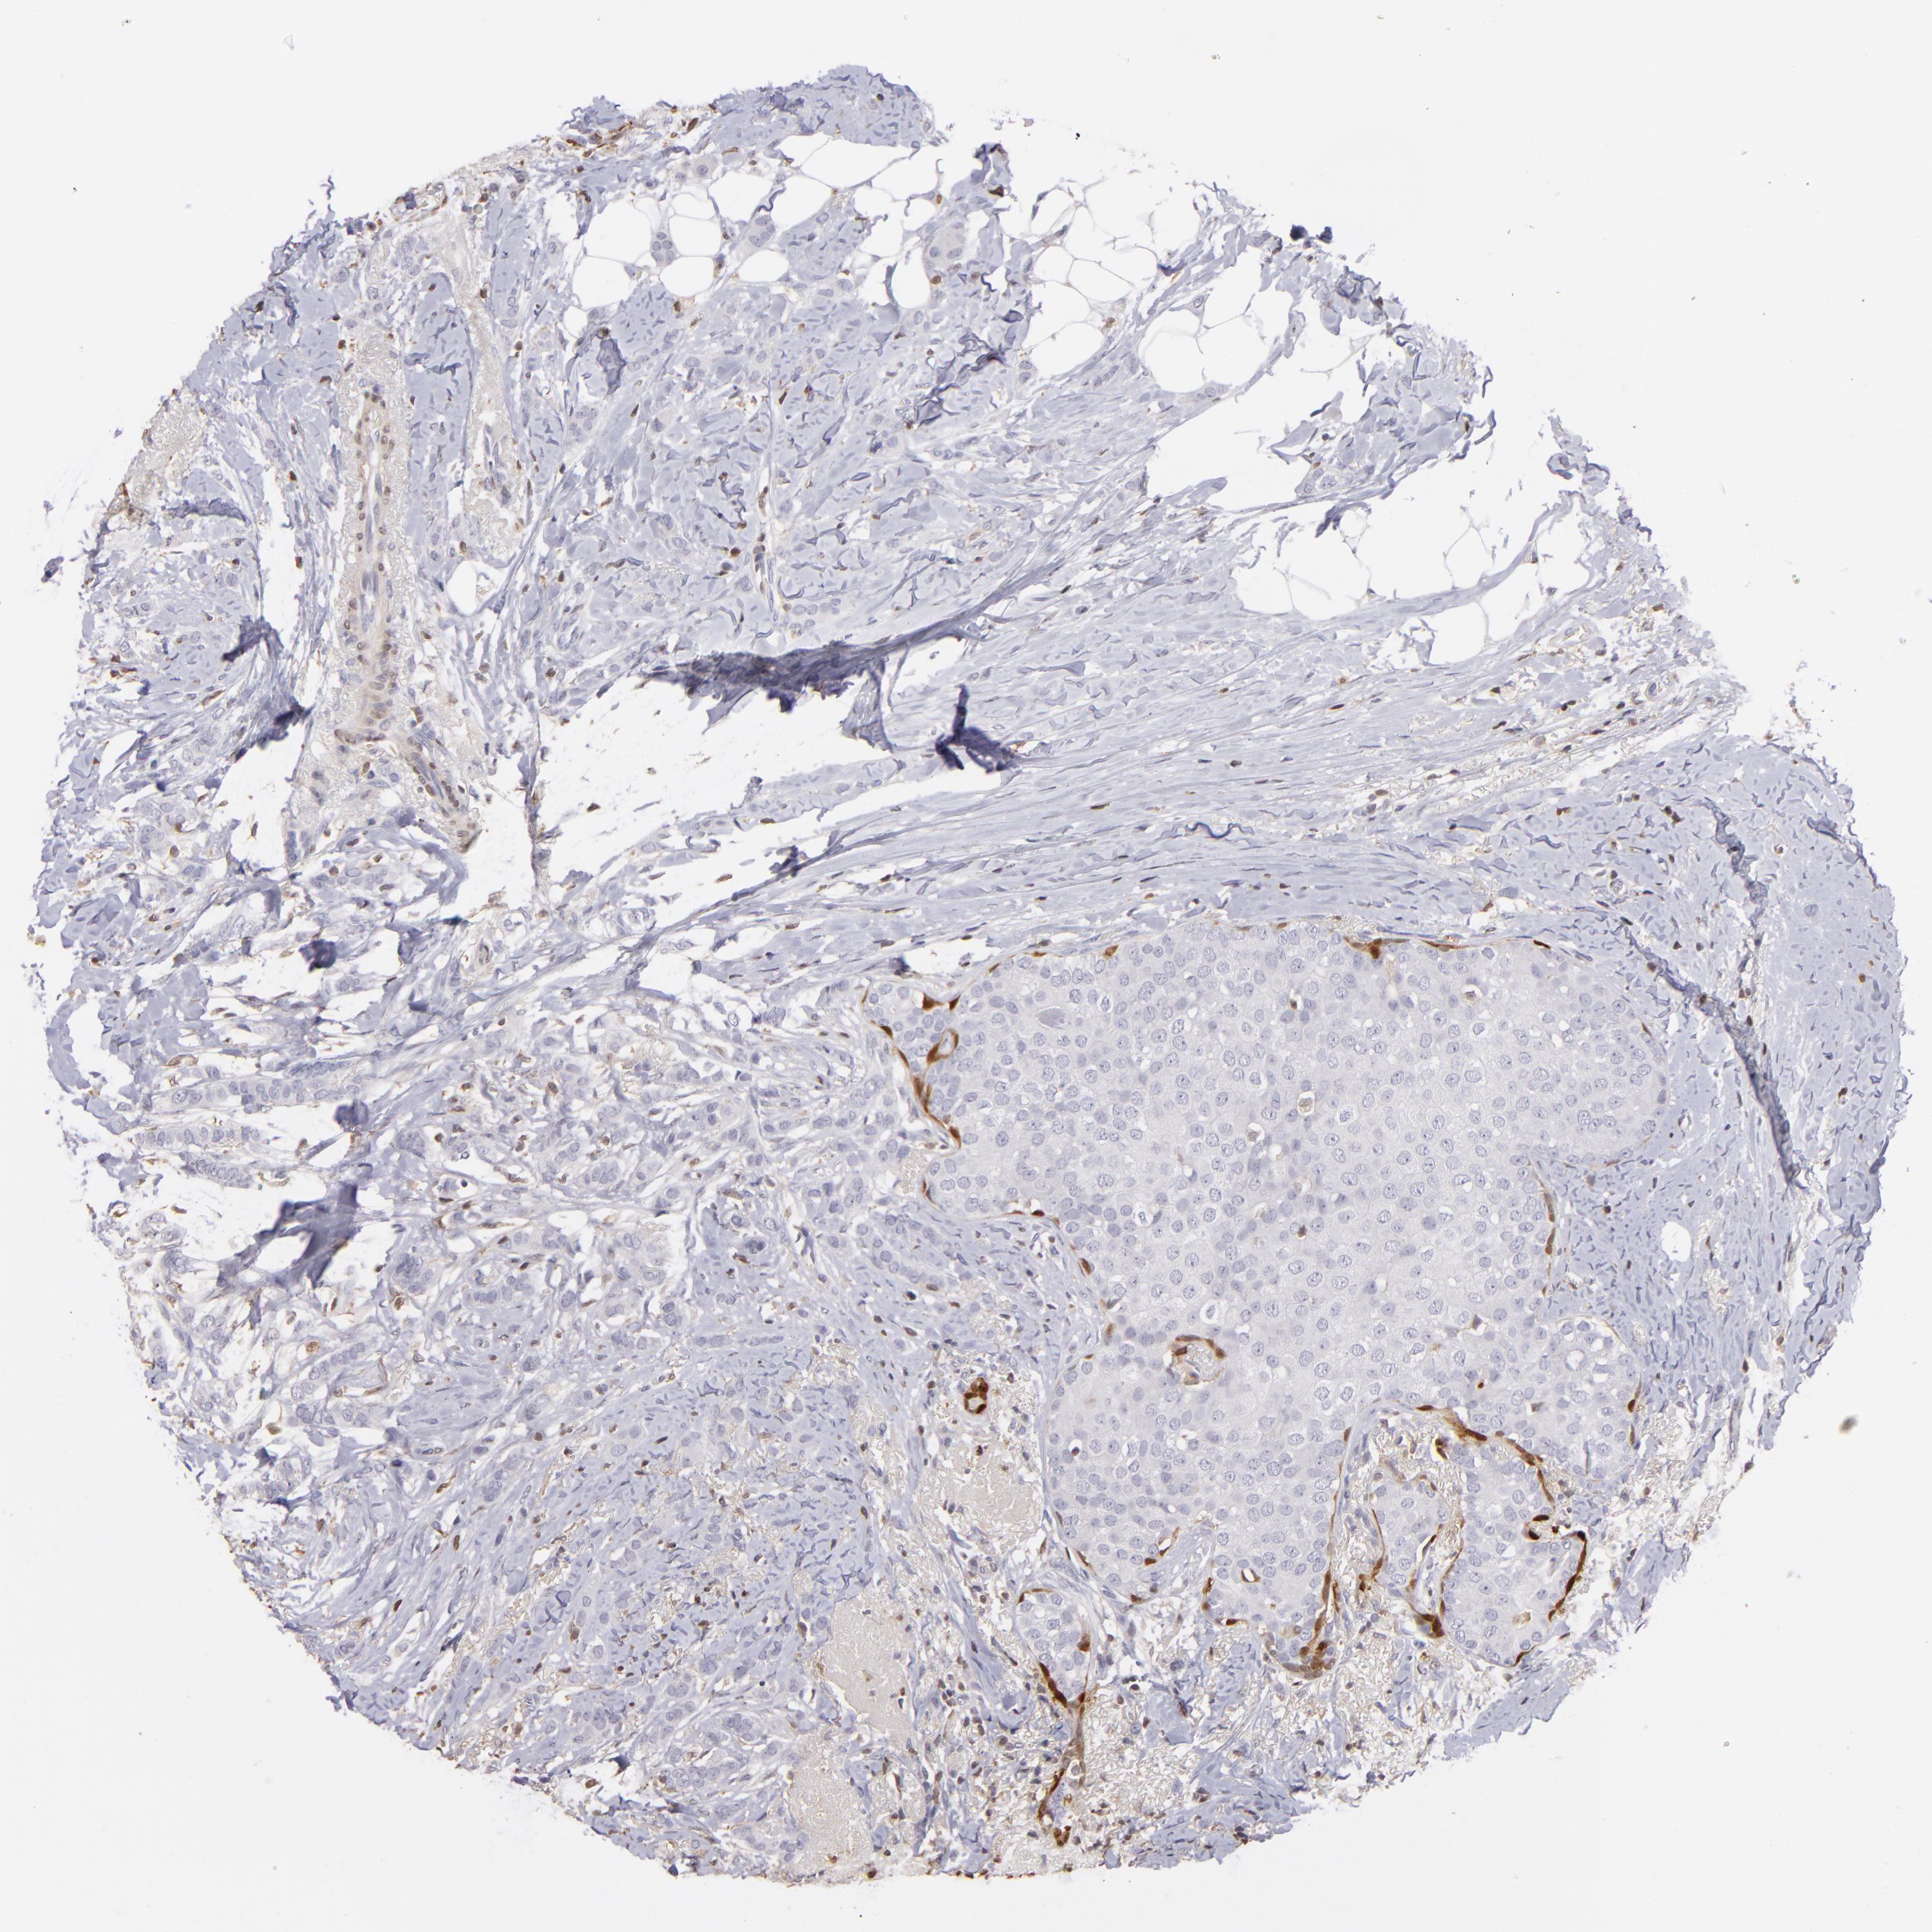

CANCER BREAST CANCER Show tissue menu

BRCA TCGA BRCA VALIDATION PROTEIN EXPRESSION